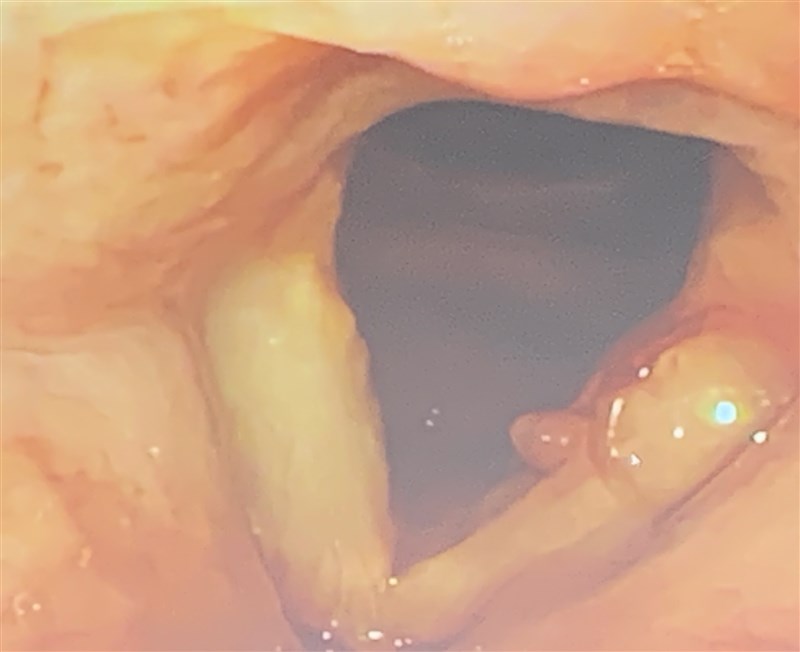

音樂系講師潘絃融過度使用聲帶,造成聲帶長繭且發聲困難,經醫院採精準注射療程,讓嗓音重現且無傷疤。圖/記者王淑芬

潘絃融表示,去年中發現難以發聲,一度以為感冒、確診新冠肺炎,經成藥、診所治療未見改善,到高醫才被檢查出聲帶長繭,大大的瘜肉影響他的發聲。一開始很擔心全身麻醉的傳統手術,還有術後結痂的問題,所幸醫療團隊建議採精準類固醇聲帶注射治療方式,很快就在門診進行並配合語言治療,終於看到瘜肉慢慢消失了。

圖/記者王淑芬